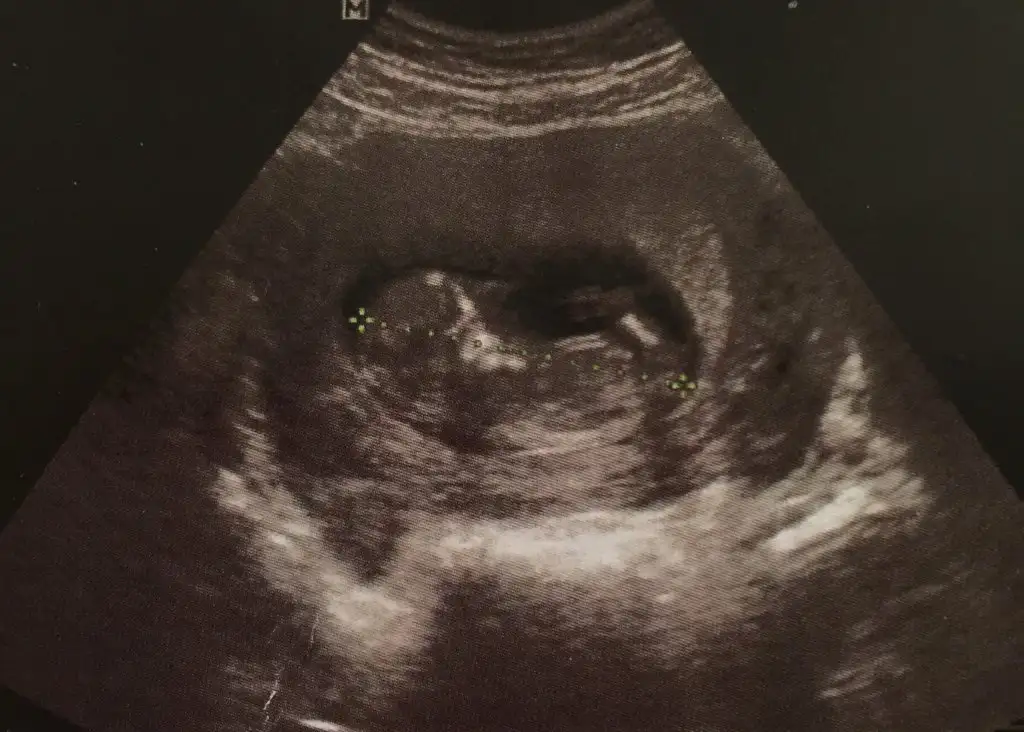

Bencede erkek...benmkine erkek mi diyorsunz :)

Teşekkür ederim. Bugün doktor da erkek ama hazırlık yapmayın daha erken dedi kesinlik olmayınca insan merak ediyorSırtı dönük bu bebisin baska foto varsa bakayim bana erkek geldi kordonu parelel olsada

Emin olamadim paralel gorunuyo ama erkek bence ..